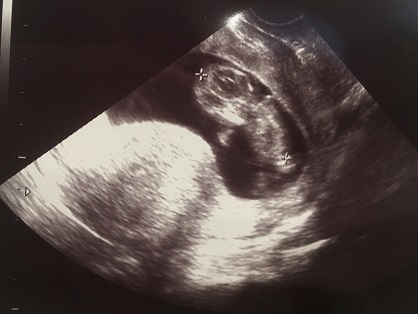

11週3日(11w3d・性別不明)|345 さん(35歳)

エコー写真撮影時のエピソード:

初めて主人付き添いでの健診。ぴょこんぴょこん跳ねたり伸びたり元気な赤ちゃんが見れました。

お医者さんも、「今日はパパも居るからご機嫌だね~。」って言ってくれてとても暖かい気持ちになりました。 写真は何枚か撮っていただいた中の顔が写っているものです。 手を顔の横に置いて寝ている姿は主人そっくり。 会えるのが楽しみです。